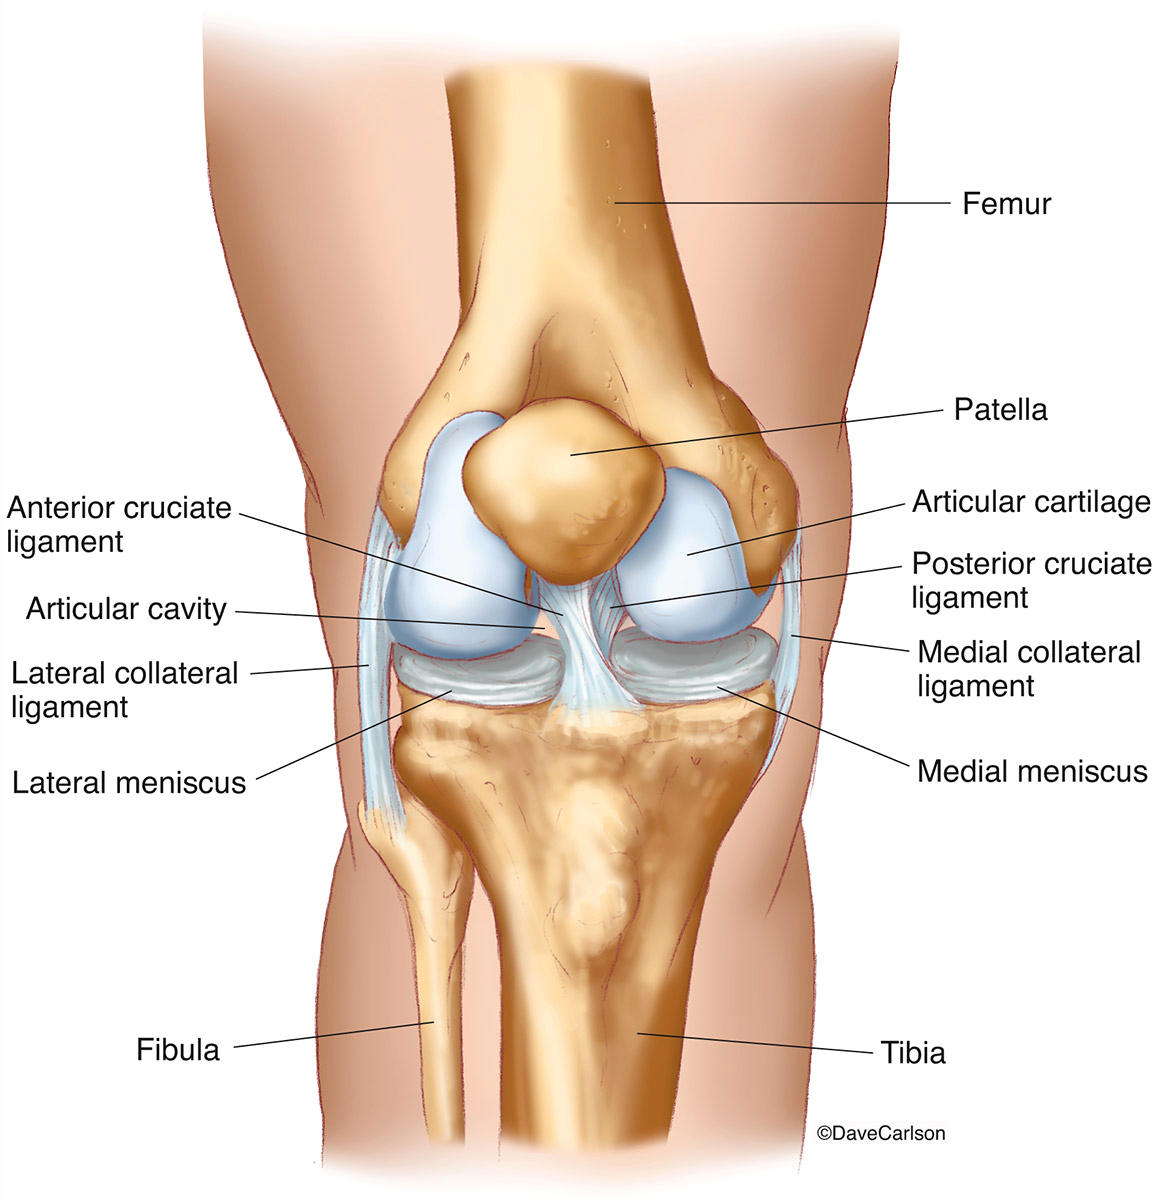

Анатомические рисунки суставов человека

:max_bytes(150000):strip_icc()/knee-anatomy--artwork-452427829-599d8b9b22fa3a0011f2030d.jpg)